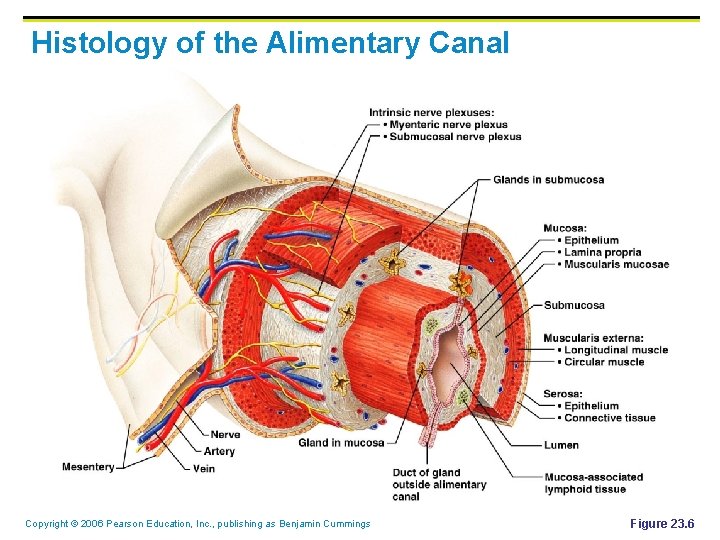

Histology of the Alimentary Canal Copyright © 2006 Pearson Education, Inc. , publishing as Benjamin Cummings Figure 23. 6